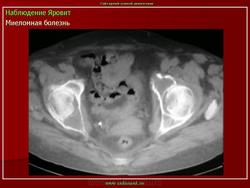

Миеломная болезнь